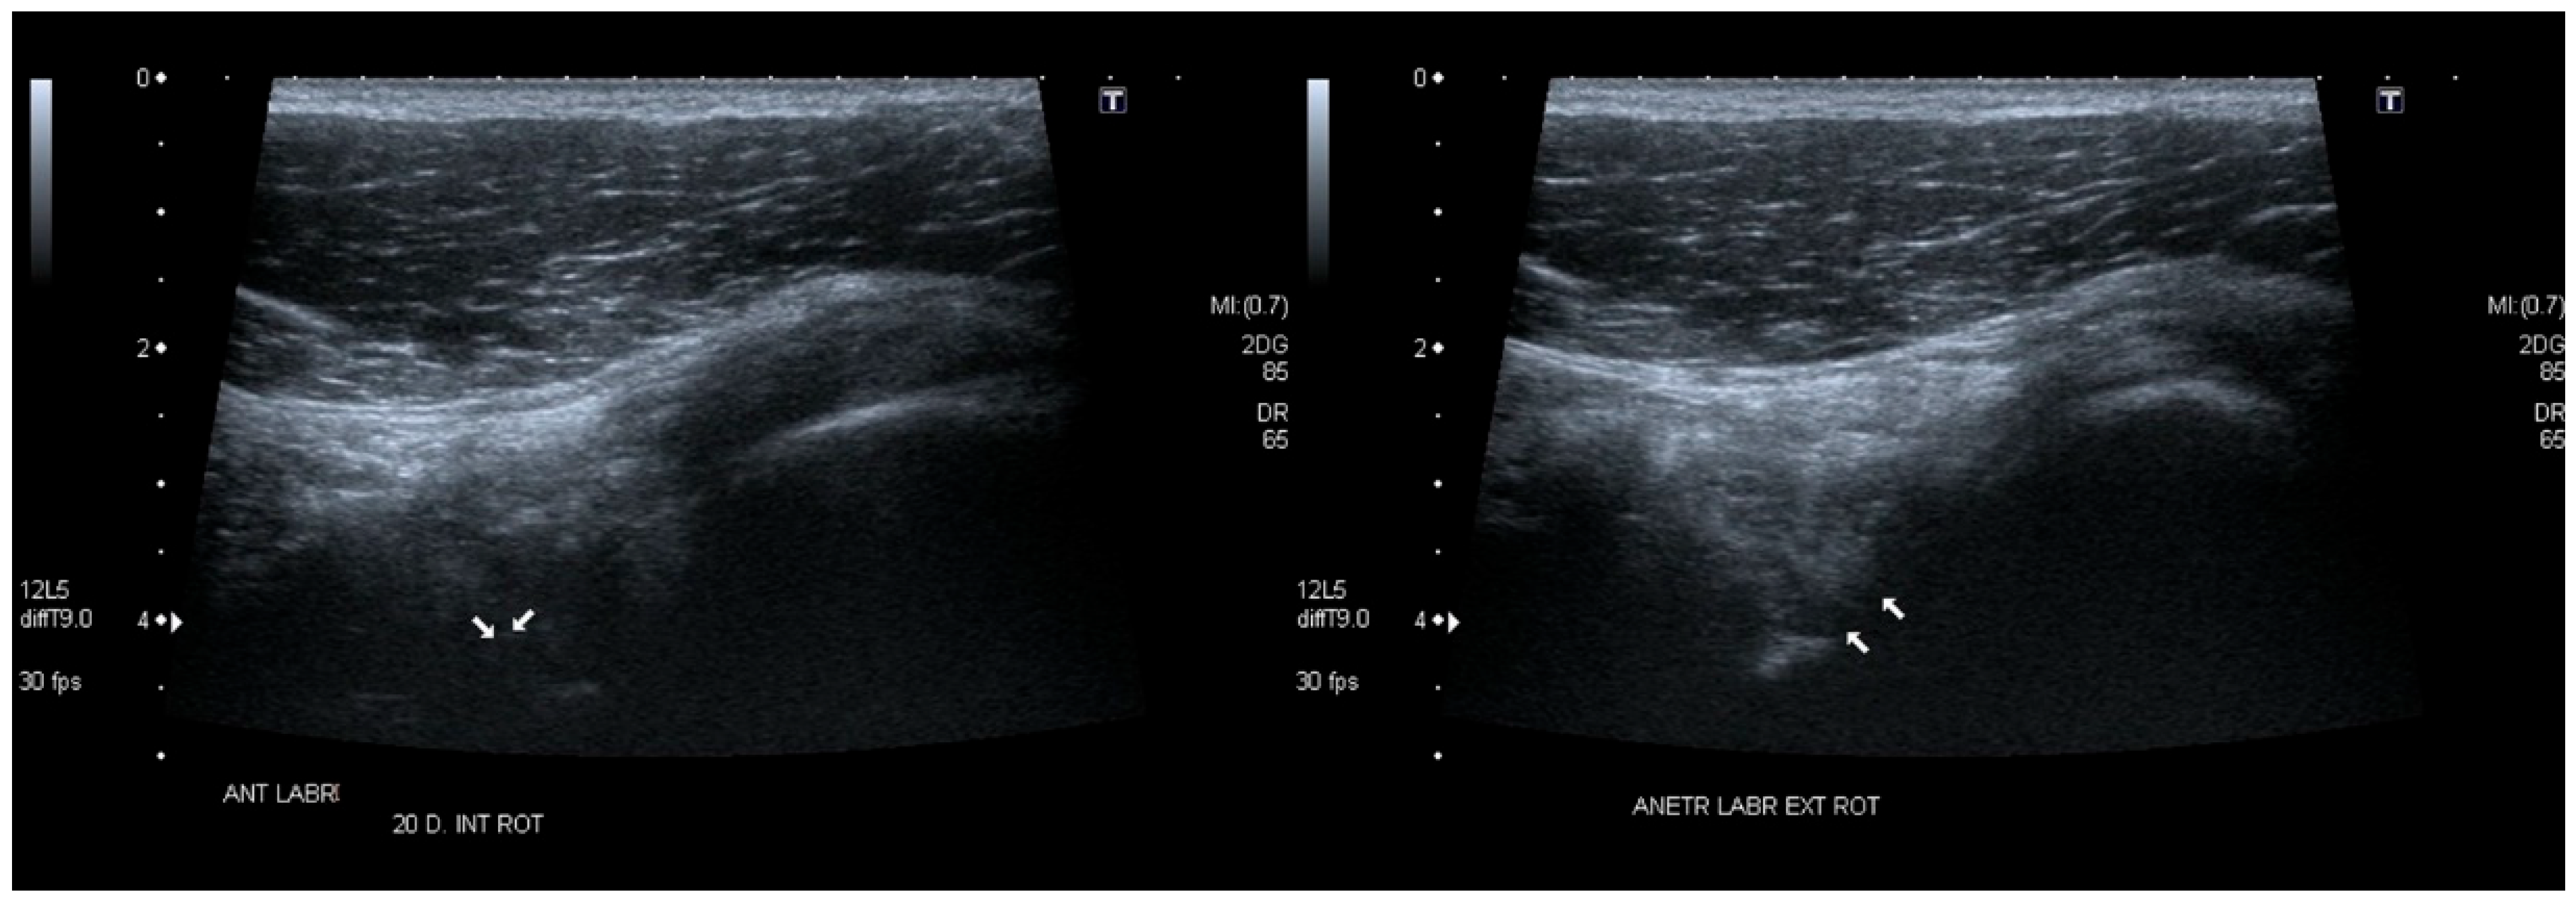

Figure 14. Superior labrum—12 o’clock position. Convex transducer (1–6 MHz). (Left image): superior labral tear (open arrow) of the right shoulder with displacement toward the joint interior. (Right image): intact superior labrum (white arrow) on the left side. Sixteen-year-old strength athlete.